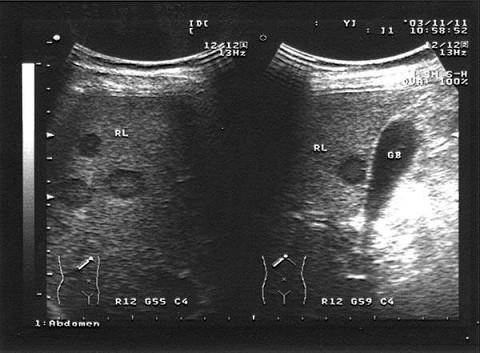

女,52岁,右上腹不适,CT示卵巢占位,结合超声声像图,诊断为?(?)A.肝囊肿B.肝包虫病C.转移性肝癌D.肝脓肿E.肝血管瘤

问题 女,52岁,右上腹不适,CT示卵巢占位,结合超声声像图,诊断为?(?)

选项 A.肝囊肿 B.肝包虫病 C.转移性肝癌 D.肝脓肿 E.肝血管瘤

答案 C